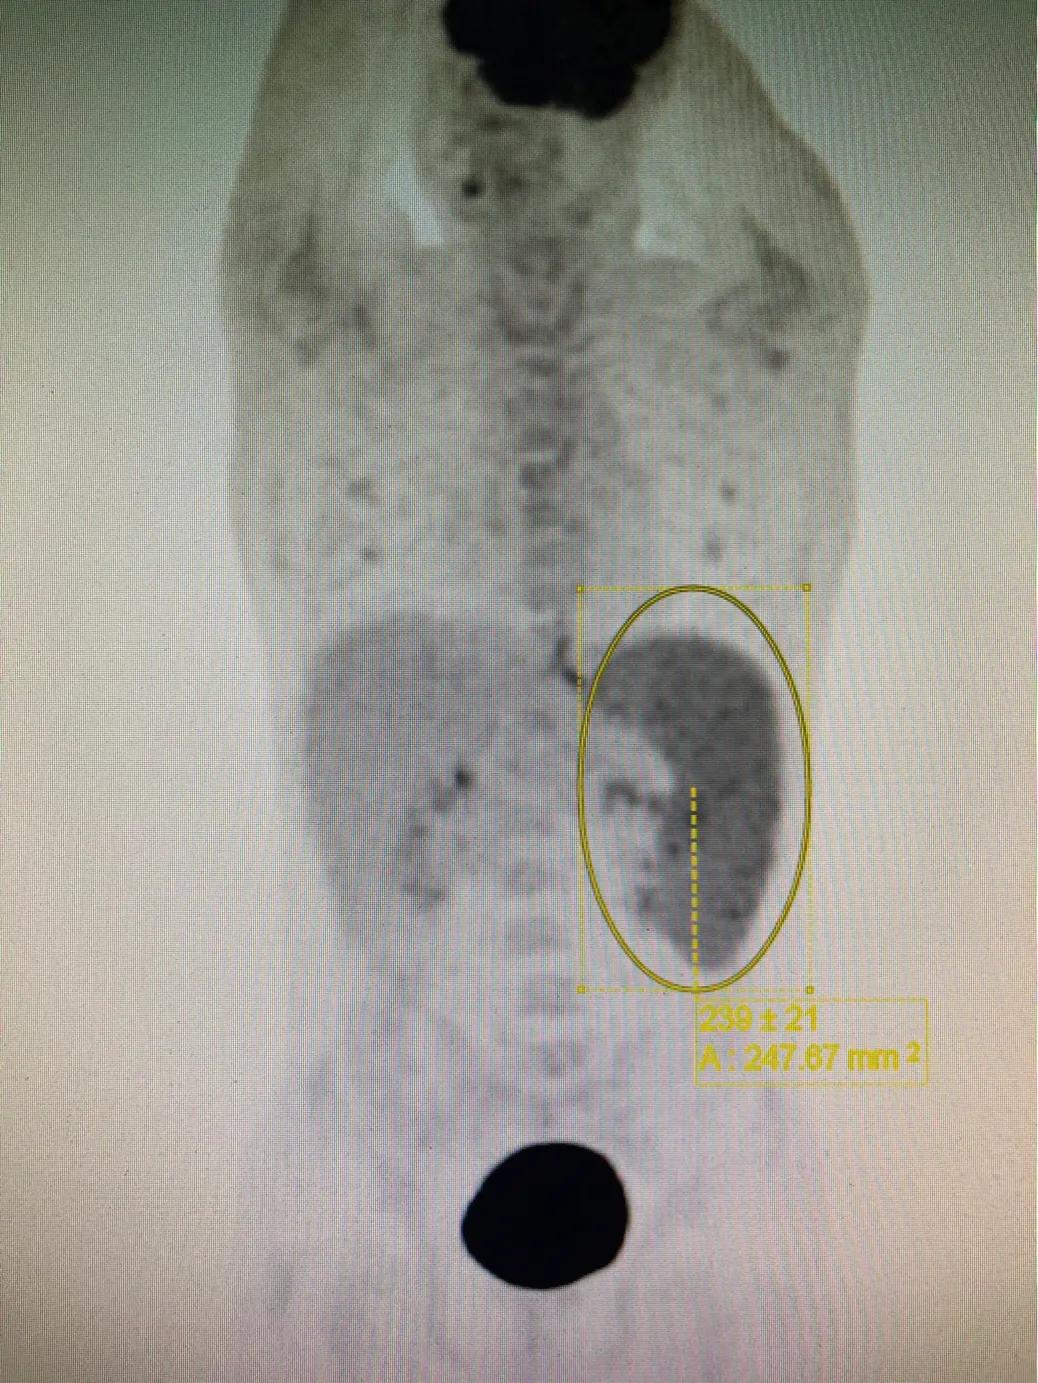

该图片提示脾脏增大